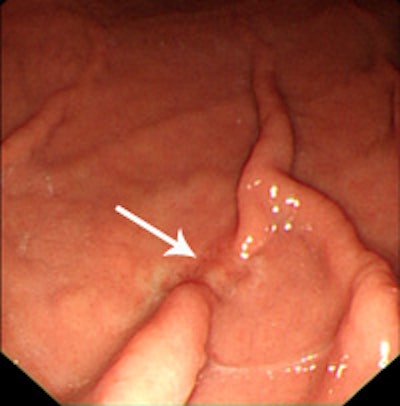

Above: Axial CT image shows questionable thickening and enhancement of inner mucosal layer (arrow). Bottom left: Virtual gastroscopic image clearly shows ulcerative lesion with abrupt termination of folds at the same location as axial CT image. Bottom right: Conventional gastroscopic image reveals a malignant ulcer with abrupt termination of gastric folds. This lesion was diagnosed as early gastric cancer on biopsy. Images courtesy of Dr. Jin Woong Kim and Dr. Sang Soo Shin.The degree of gastric distension was considered to be adequate when the gastric lumen was distended greater than 50% of the expected maximal luminal distension. Single-phase (portal venous phase) contrast-enhanced CT was performed after intravenous injection of 100 to 150 mL of iodinated contrast material with a power injector (Empowered CTA, E-Z-EM) at a rate of 3 mL/sec through an antecubital vein. The total amount of injected contrast material was adjusted according to the body weight of the patients (2 mL/kg).

Overall, gastric cancer was identified in 123 (96.9%) of the 127 cancers on the CT images. Four undetectable cancers on CT were pathologically staged as T1a (n = 3) and T1b (n = 1), respectively. In cases of early gastric cancer (EGC), 56 (73.7%) of the 76 cancers were visible on both the 2D and the 3D images, whereas EGC was identified only on the 2D and the 3D images in two (2.6%) and 14 (18.4%) cancers, respectively.